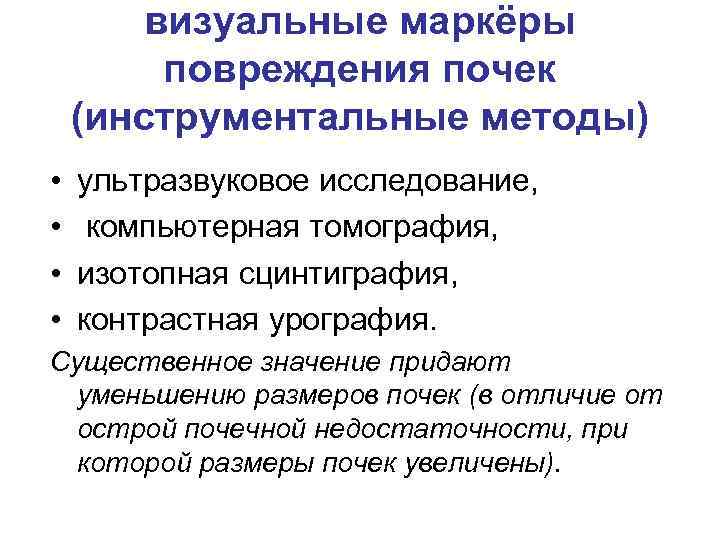

визуальные маркёры повреждения почек (инструментальные методы) • • ультразвуковое исследование, компьютерная томография, изотопная сцинтиграфия, контрастная урография. Существенное значение придают уменьшению размеров почек (в отличие от острой почечной недостаточности, при которой размеры почек увеличены).

визуальные маркёры повреждения почек (инструментальные методы) • • ультразвуковое исследование, компьютерная томография, изотопная сцинтиграфия, контрастная урография. Существенное значение придают уменьшению размеров почек (в отличие от острой почечной недостаточности, при которой размеры почек увеличены).